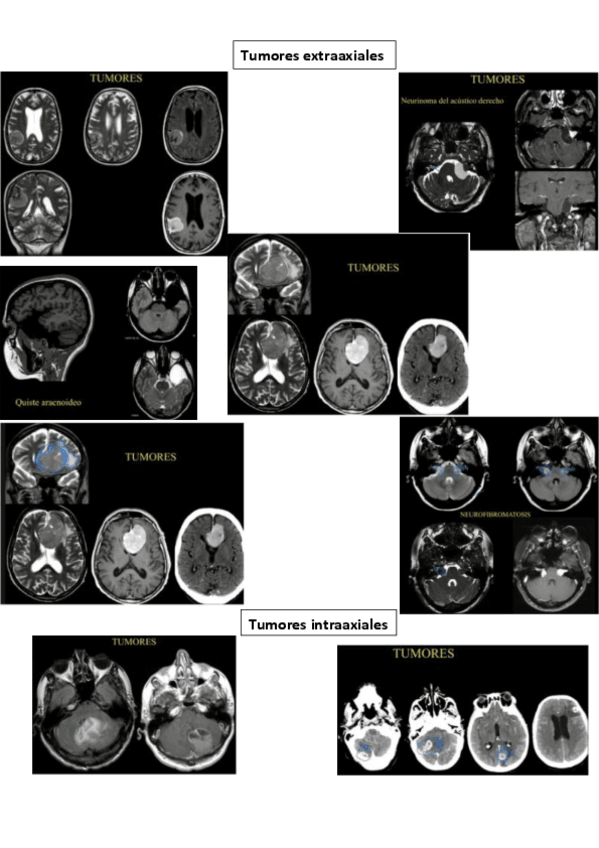

Ejemplos de RX, TC, RM de las enfermedades que hemos visto en clase o en prácticas. NO son fotos de clase ni de prácticas

BLOQUE-MUSCULO-ESQUELETICO.pdf